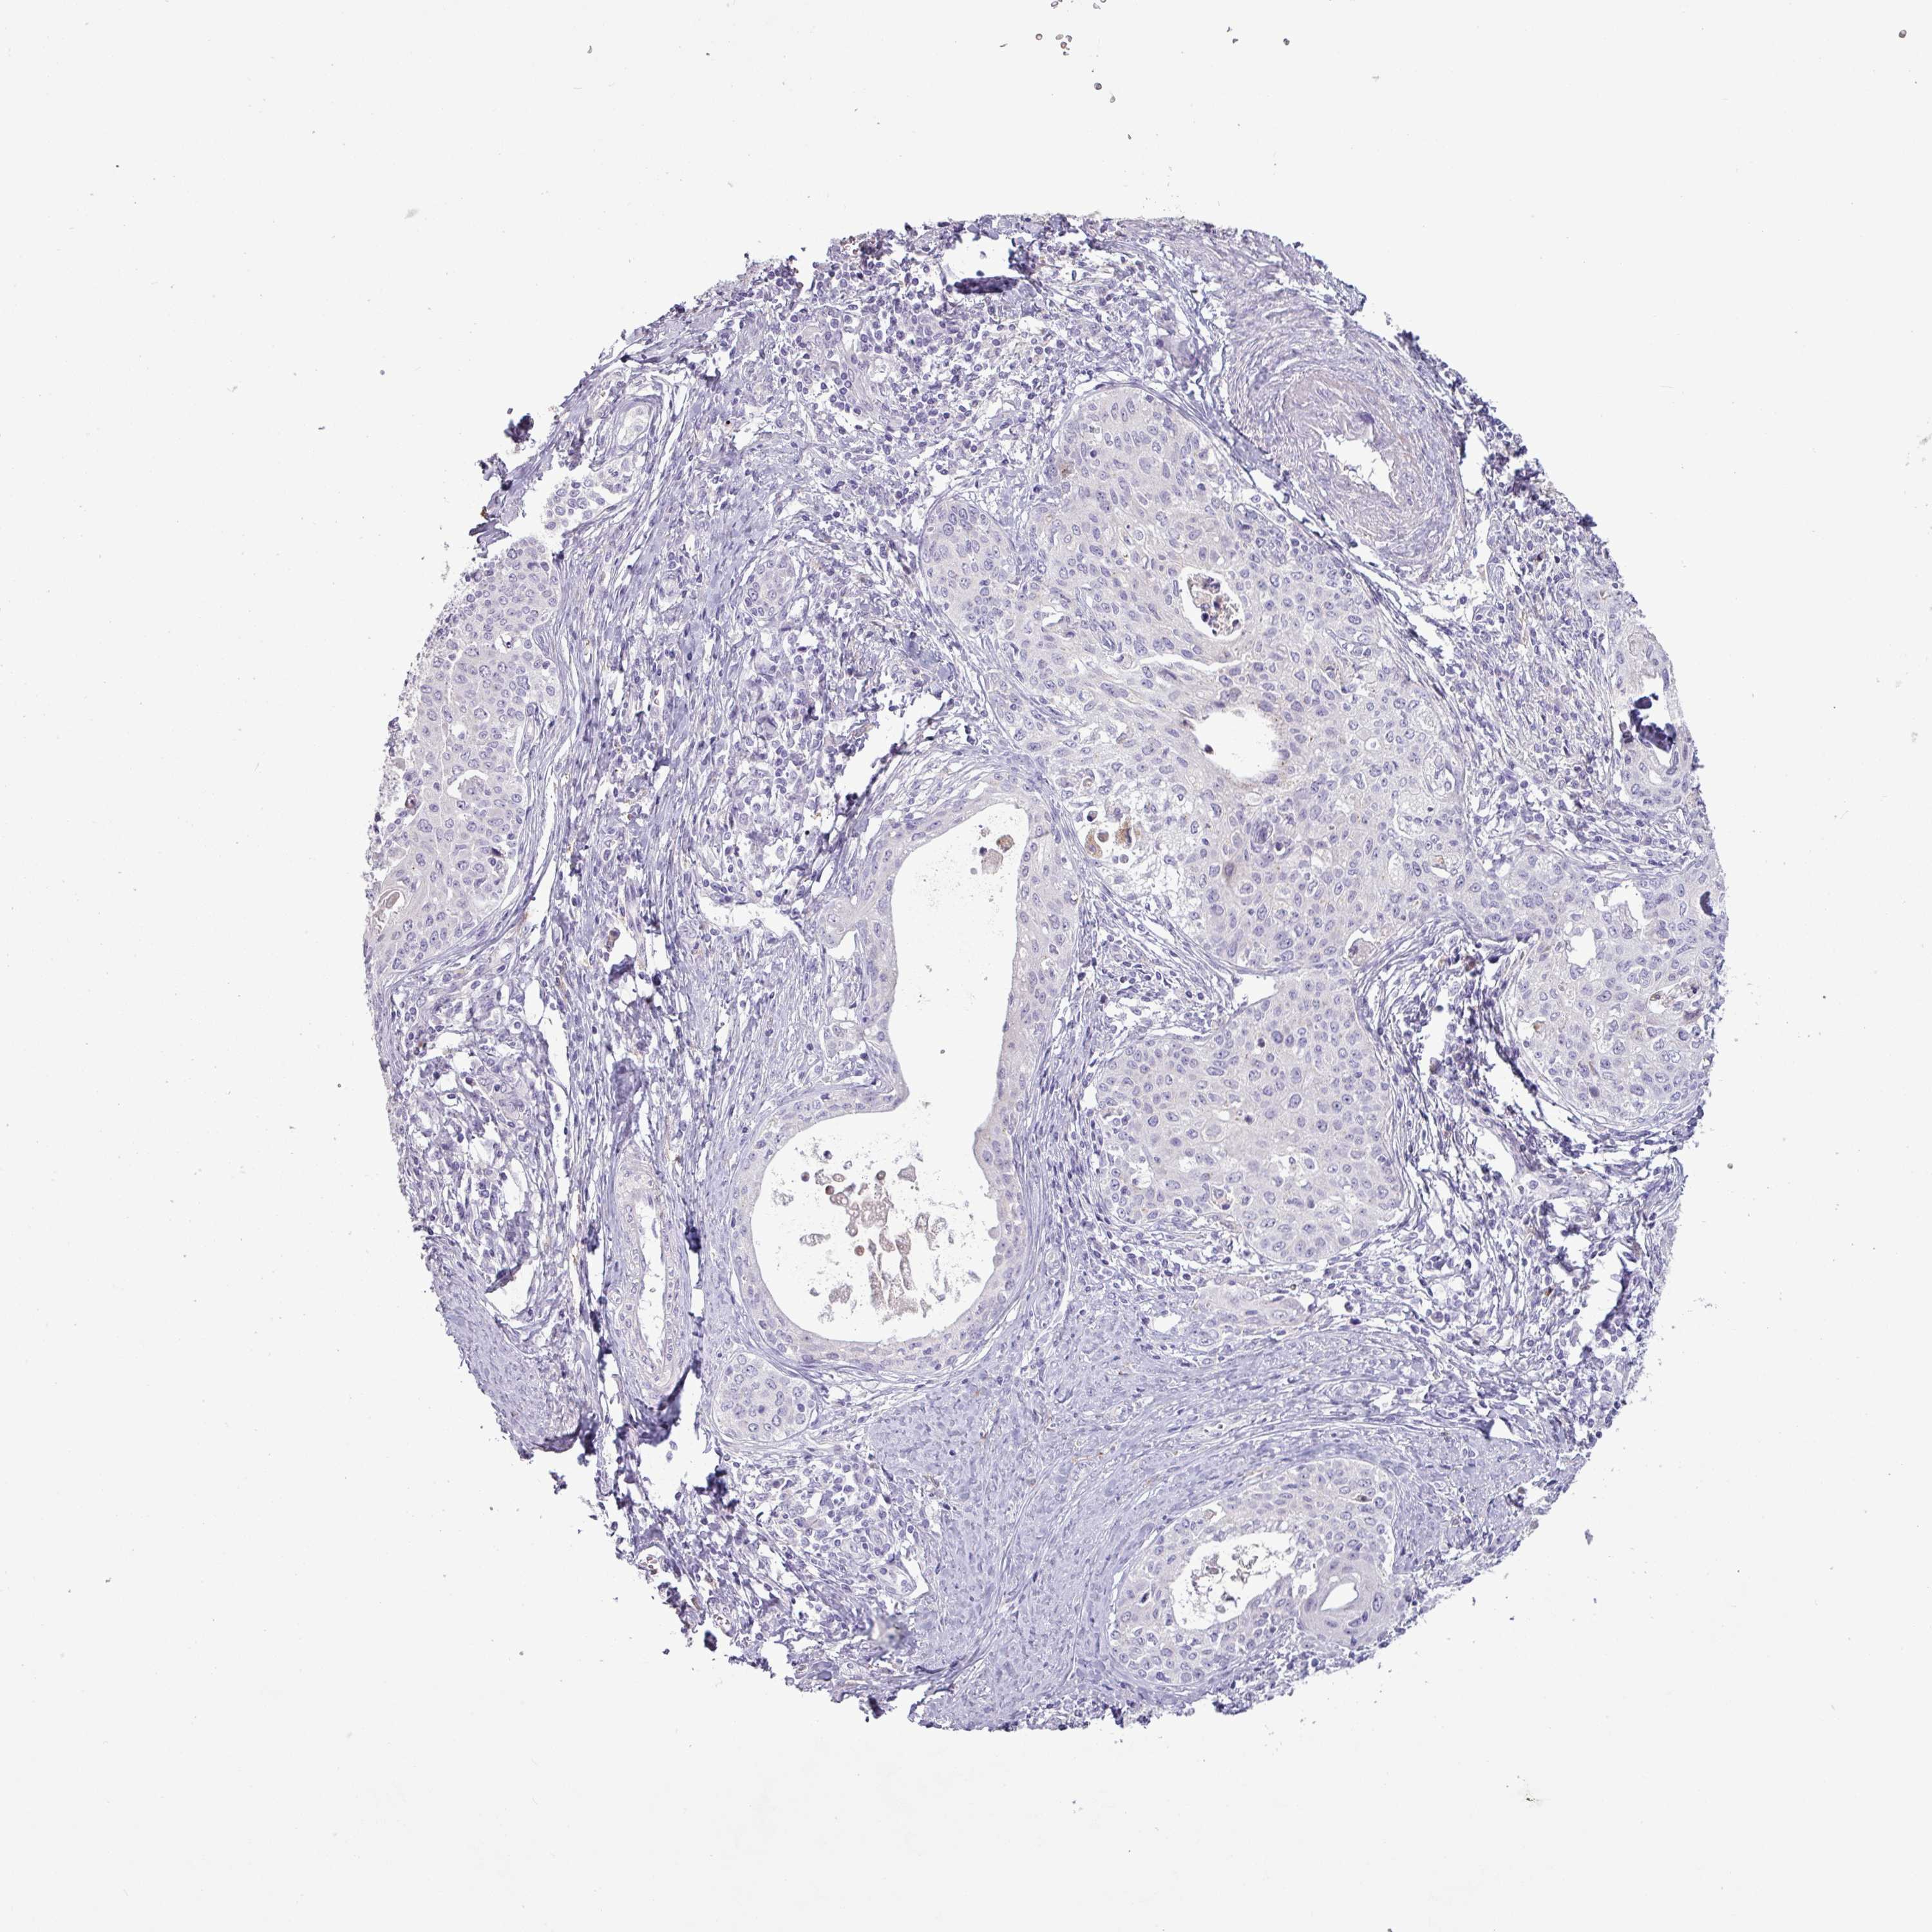

CERVICAL CANCER - Protein expressioni

A mouse-over function shows sample information and annotation data. Click on an image to view it in a full screen mode. Samples can be filtered based on level of antibody staining by selecting one or several of the following categories: high, medium, low and not detected. The assay and annotation is described here.

Note that samples used for immunohistochemistry by the Human Protein Atlas do not correspond to samples in the TCGA dataset.

Antibody stainingi

Antibody staining in the annotated cell types in the current human tissue is reported as not detected, low, medium, or high, based on conventional immunohistochemistry profiling in selected tissues. This score is based on the combination of the staining intensity and fraction of stained cells.

Each image is clickable and will lead to virtual microscopy that enables deeper exploration of all samples and also displays staining intensity scores, fraction scores and subcellular localization as well as patient and tissue information for each sample.

Squamous cell carcinoma, NOS